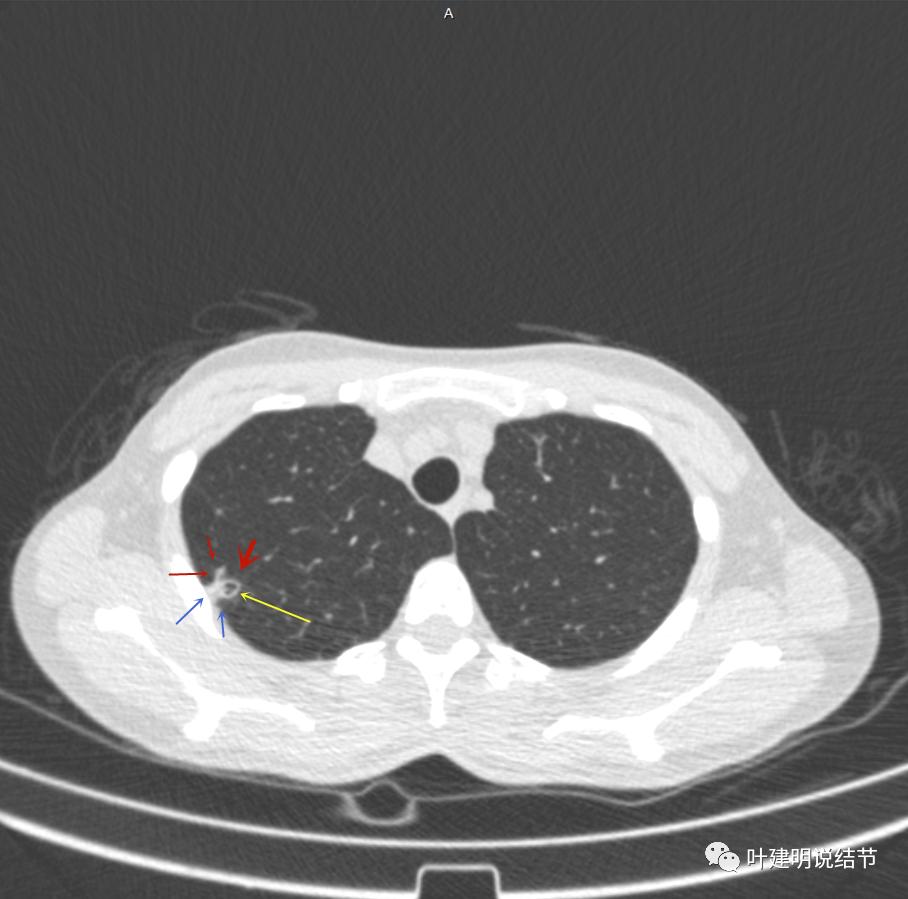

邻近胸膜明显增厚,且广基底,主病灶前方有小片磨玻璃影

主病灶与胸膜间基本相连,模糊清(蓝色箭头),主病灶壁厚薄欠均,边上有高密度条索状(桔色箭头)